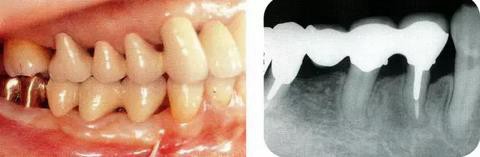

圖17-4(左),5 (右)  術(shù)后9年的口腔內(nèi)照片和X線片,牙槽嵴平坦化,牙周探診數(shù)值很小。